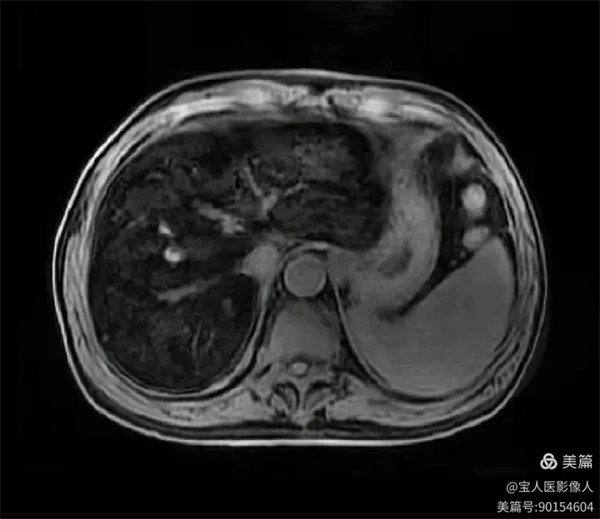

T2WI冠位,軸位,肝實(shí)質(zhì)信號(hào)明顯降低,呈“”黑肝征”,而脾臟信號(hào)正常。